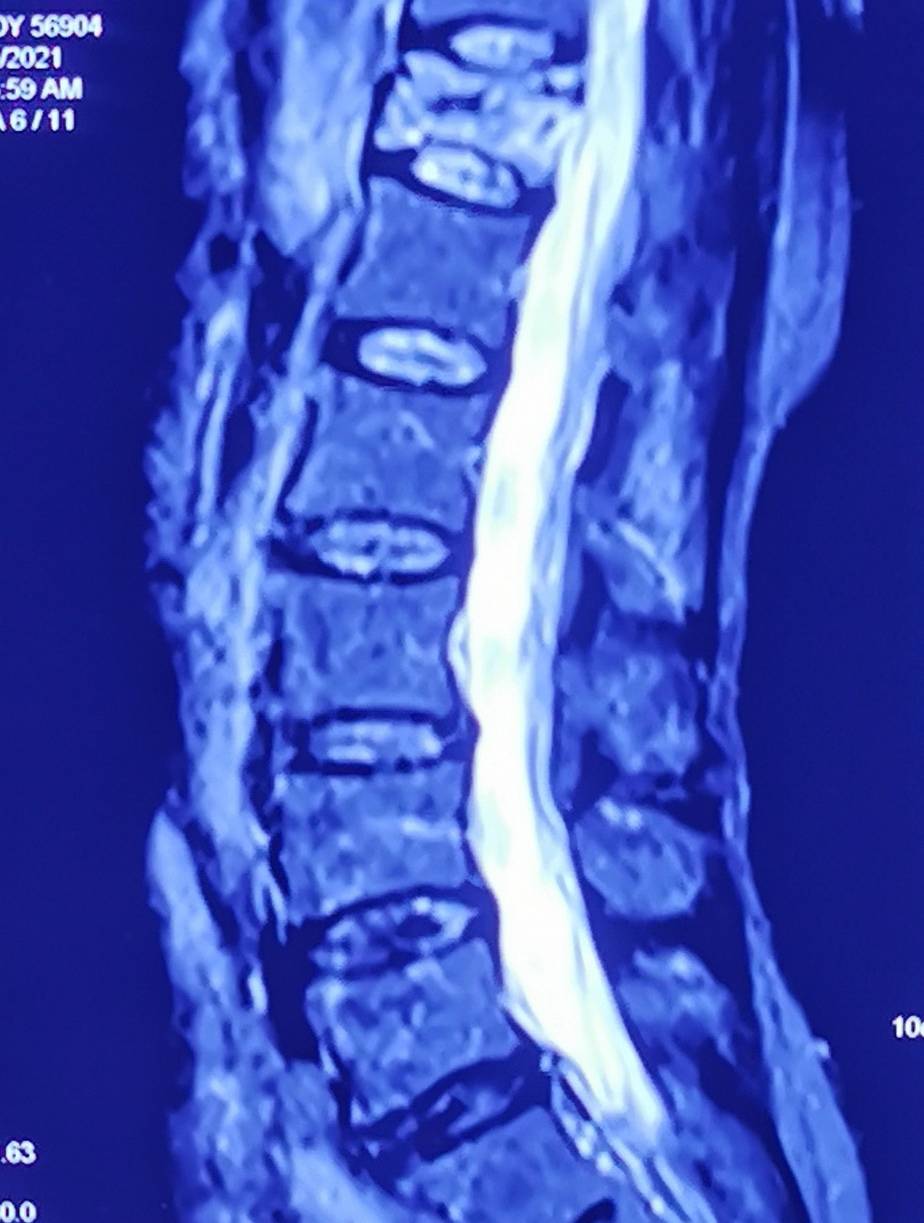

【癌症|【读报】腰背长期疼警惕恶性肿瘤】据《大众卫生报》:张大爷3个月前无故出现腰背部疼痛伴右大腿疼痛 , 偶尔咳嗽咳痰 , 在当地医院做了很多检查 , 吃了很多镇痛药 , 也做过理疗、神经阻滞治疗 , 均没有明显效果 , 后在湖南省肿瘤医院经PET-CT检查后确诊为肺癌晚期 , 并脑、肾、肝、腹膜后及椎体广泛转移 。 对此 , 专家提醒 , 当身体某部位发生不明原因的疼痛且长时间无法缓解时 , 应及早就医 , 警惕癌症可能 该院麻醉手术中心主任杨金凤表示 , 对于新发或者确诊的癌症患者来说 , 腰背疼痛往往是一个非常明显的信号 。 数据显示 , 约有1/4新诊断为恶性肿瘤的患者、1/3正在接受治疗的患者、3/4晚期肿瘤患者合并有疼痛症状 。 然而 , 很多患者把长时间腰背痛当作腰椎间盘突出症等疾病而采取相关治疗 , 其结果往往是疼痛无法缓解 , 导致最后确诊时已是肿瘤晚期 。杨金凤解释 , 当恶性肿瘤发生骨转移时往往会出现疼痛 , 肺癌、乳腺癌、前列腺癌等均易发生骨转移 。 骨转移的疼痛一般呈间歇性或持续性 , 夜间更加明显 , 易被误诊、漏诊 。 因此 , 有顽固性腰背痛的人一定不能掉以轻心 , 需及时到医院检查 , 包括肿瘤标志物、特异性指标、血沉、C反应蛋白等实验室指标 , 超声、CT、PET-CT等影像学检查 , 以及病理诊断 , 做到早发现 , 早治疗 。

- 体内有癌,腰背先知晓?出现这2种标志,或是癌症“警告”?